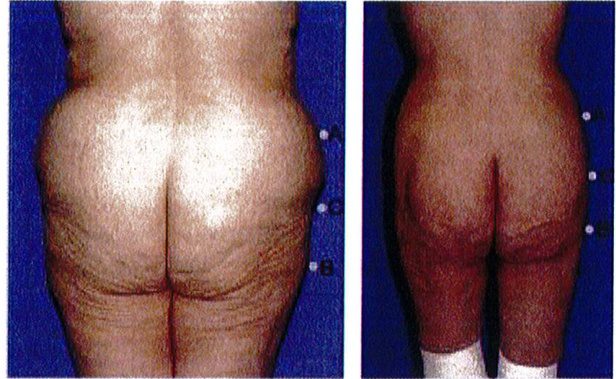

Hình 1. (A) Hình thể toàn bộ vùng mông phụ thuộc vào khung xương, cơ mông lớn, vị trí và lượng mỡ dưới da, độ căng của da. (B) Khung mông, với cơ môna lớn đã được tách ra.

Over rall Buttock Shape : Hình thể toàn bộ vùng mông Gluteal muscle: Cơ mông Gluateal muscle(gluteal shape): Hình dạng cơ mông Frame: Khung